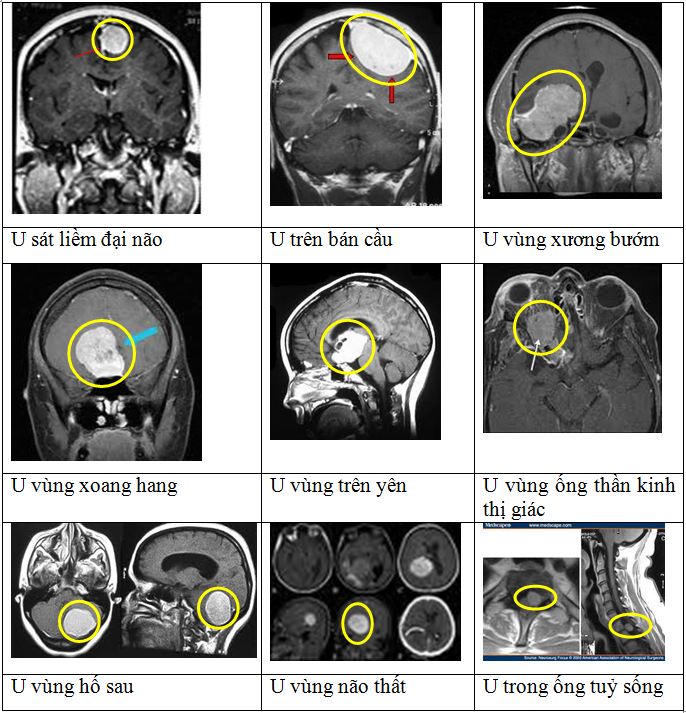

U màng não là sự phát triển bất thường của tế bào màng nhện trong hộp sọ, với đặc điểm u phát triển dọc theo "đuôi" màng não. Vì vậy u thường phát triển và xâm lấn rộng vào những vùng khác trong não bộ. U phát triển âm thầm nên triệu chứng lâm sàng rất kín đáo. Vị trí của u màng não rất đa dạng: sát liềm đại não, lồi não, vùng xương bướm (xương đá hay vùng xoang hang), vùng hố sau (thân não, tiểu não), vùng xương sàng... Phương pháp điều trị  kinh điển của u màng não là phẫu thuật lấy u. Tuy nhiên, phẫu thuật mở hộp sọ lấy u rất khó khăn với trường hợp u ở vị trí trong sâu: vùng xoang hang, hố sau hoặc vùng có nguy cơ chảy máu nhiều như u sát liềm đại não. Hơn nữa u có thể tái phát sau phẫu thuật khi không thể phẫu thuật triệt để.

Dưới đây là một số hình các vị trí của u màng não